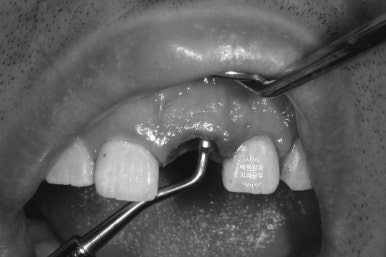

안타깝지만, 주변의 잇몸조직이 상하지 않도록, 최대한 조심히 치아뿌리 (잔존치근)를 제거하였습니다.

발치 즉시 임플란트의 핵심은 주변 조직에 위해한 영향 없이 최대한 치아뿌리만 쏙 빼내는 것입니다.!!!

제가 위에 링크 걸어드렸던, 외과적 정출술에서 사용하던 페리오톰(periotome)이라는 기구가 참 도움이 됩니다.

귀신같이 뿌리만 남아있던 앞니를 쏙 제거하는데 성공!!

보니까 뿌리는 참 건전합니다. 너무 아까웠어요..ㅠㅠㅠ 이럴 때 안타깝고 속상합니다...